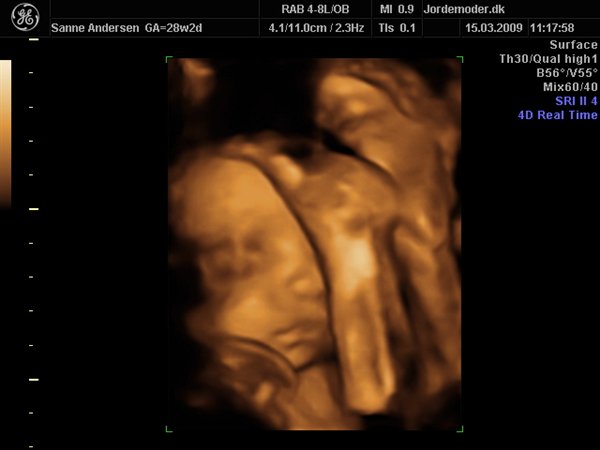

Det gik bare så godt til scanningen, men den ville meget heller sove end være aktiv så vi kunne få en masse forskellige billeder... men vi har fået en masse dejlige billeder og en dvd hvor der er masser af hjertelyd og rigtig pænt billede af hvordan hjertet slår

men vi venter en lille dreng, vi kunne desværre ikke få billede i 3d da han bare ikke ville rykke på sig og han lå så der var for meget fostervand...

Vedhæftede fotos (klik for at se i fuld størrelse)